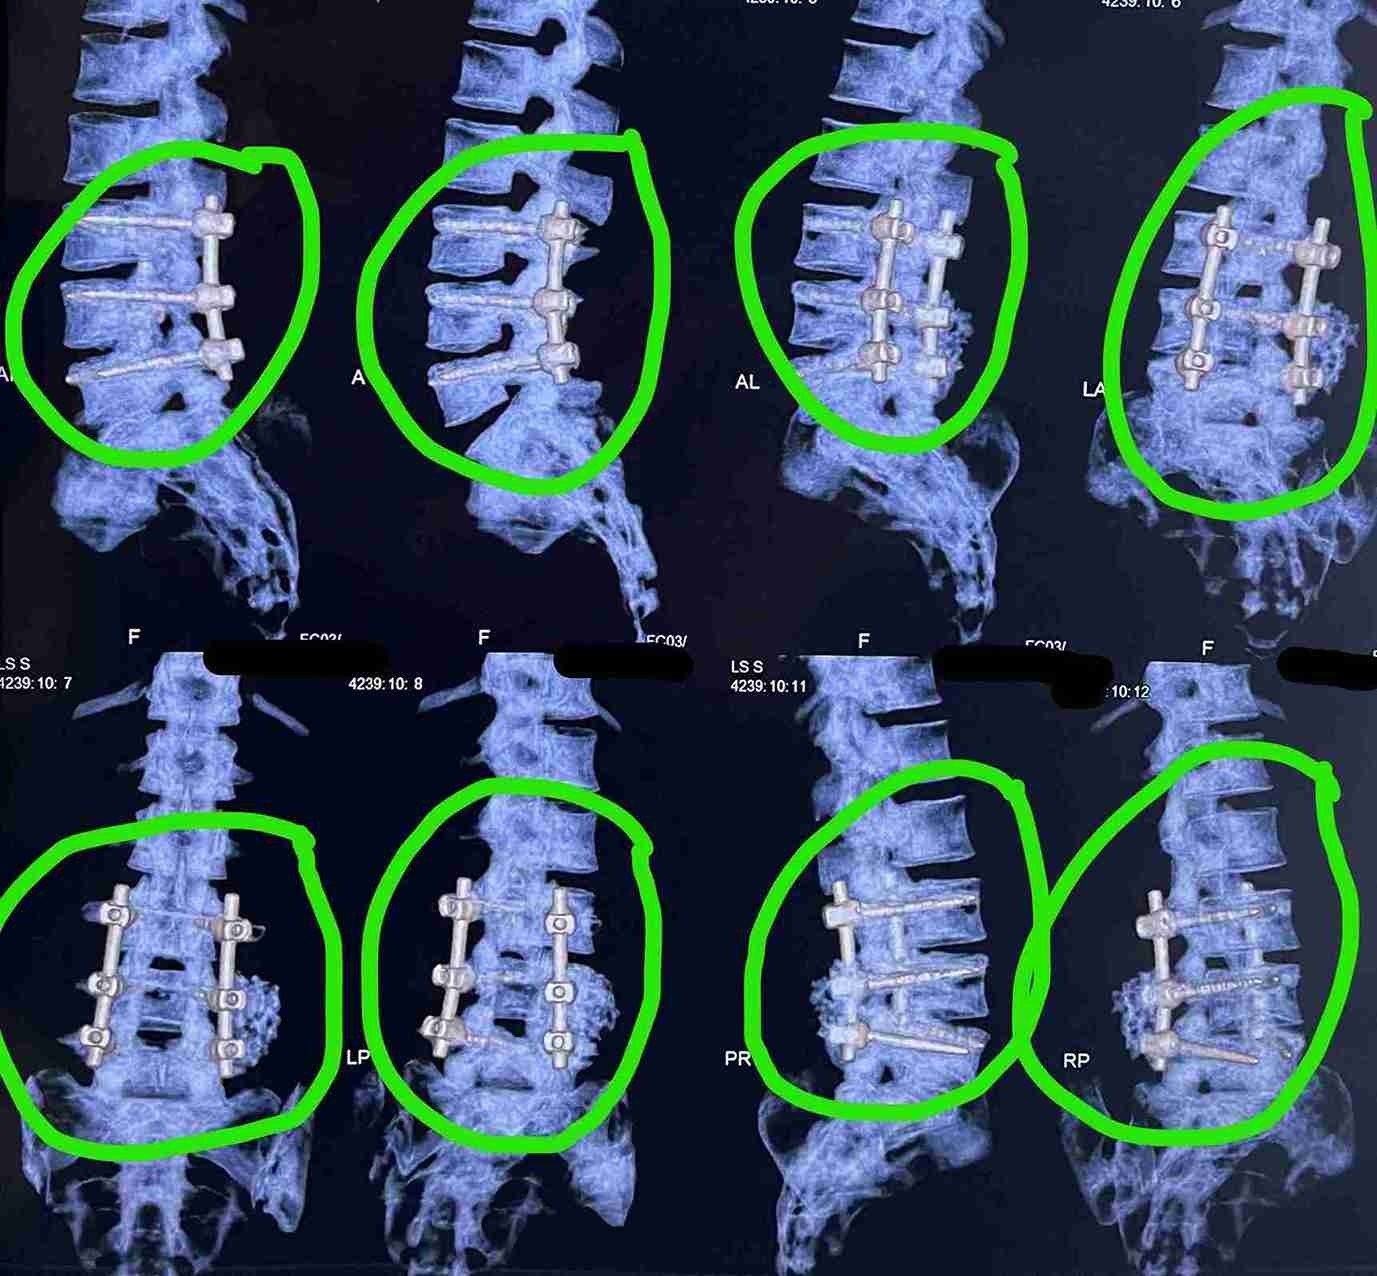

Lumbar Spinal Canal Decompression with Spinal Fusion

This specialized surgery aims to treat lumbar spinal stenosis, a condition where the spinal canal narrows and puts pressure on nerves, causing severe pain and discomfort for the patient.

• Advanced internal spinal fixation